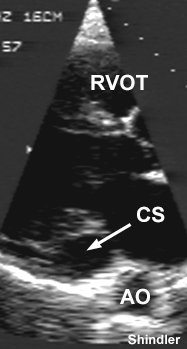

Daniel Shindler@danshindler·

#cardioPOCUS shows a dilated coronary sinus ncbi.nlm.nih.gov/pubmed/11451829 Question: What is the bedside physical finding that suggests a persistent left superior vena cava? Answer: Jugular venous pulsations are more easily visualized on the left side of the neck.